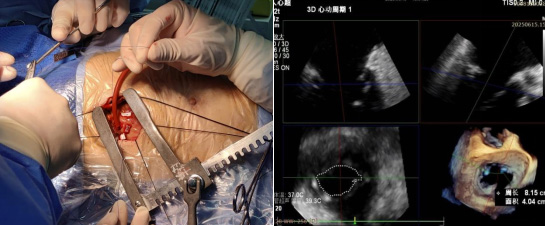

经导管二尖瓣钳夹术(TEER)

经股静脉或心尖入路钳夹二尖瓣反流区域,无需体外循环,适用于重度二尖瓣关闭不全的高危患者。应用三维超声技术,精准定位反流区域,为无法耐受开胸手术患者提供新的治疗策略。